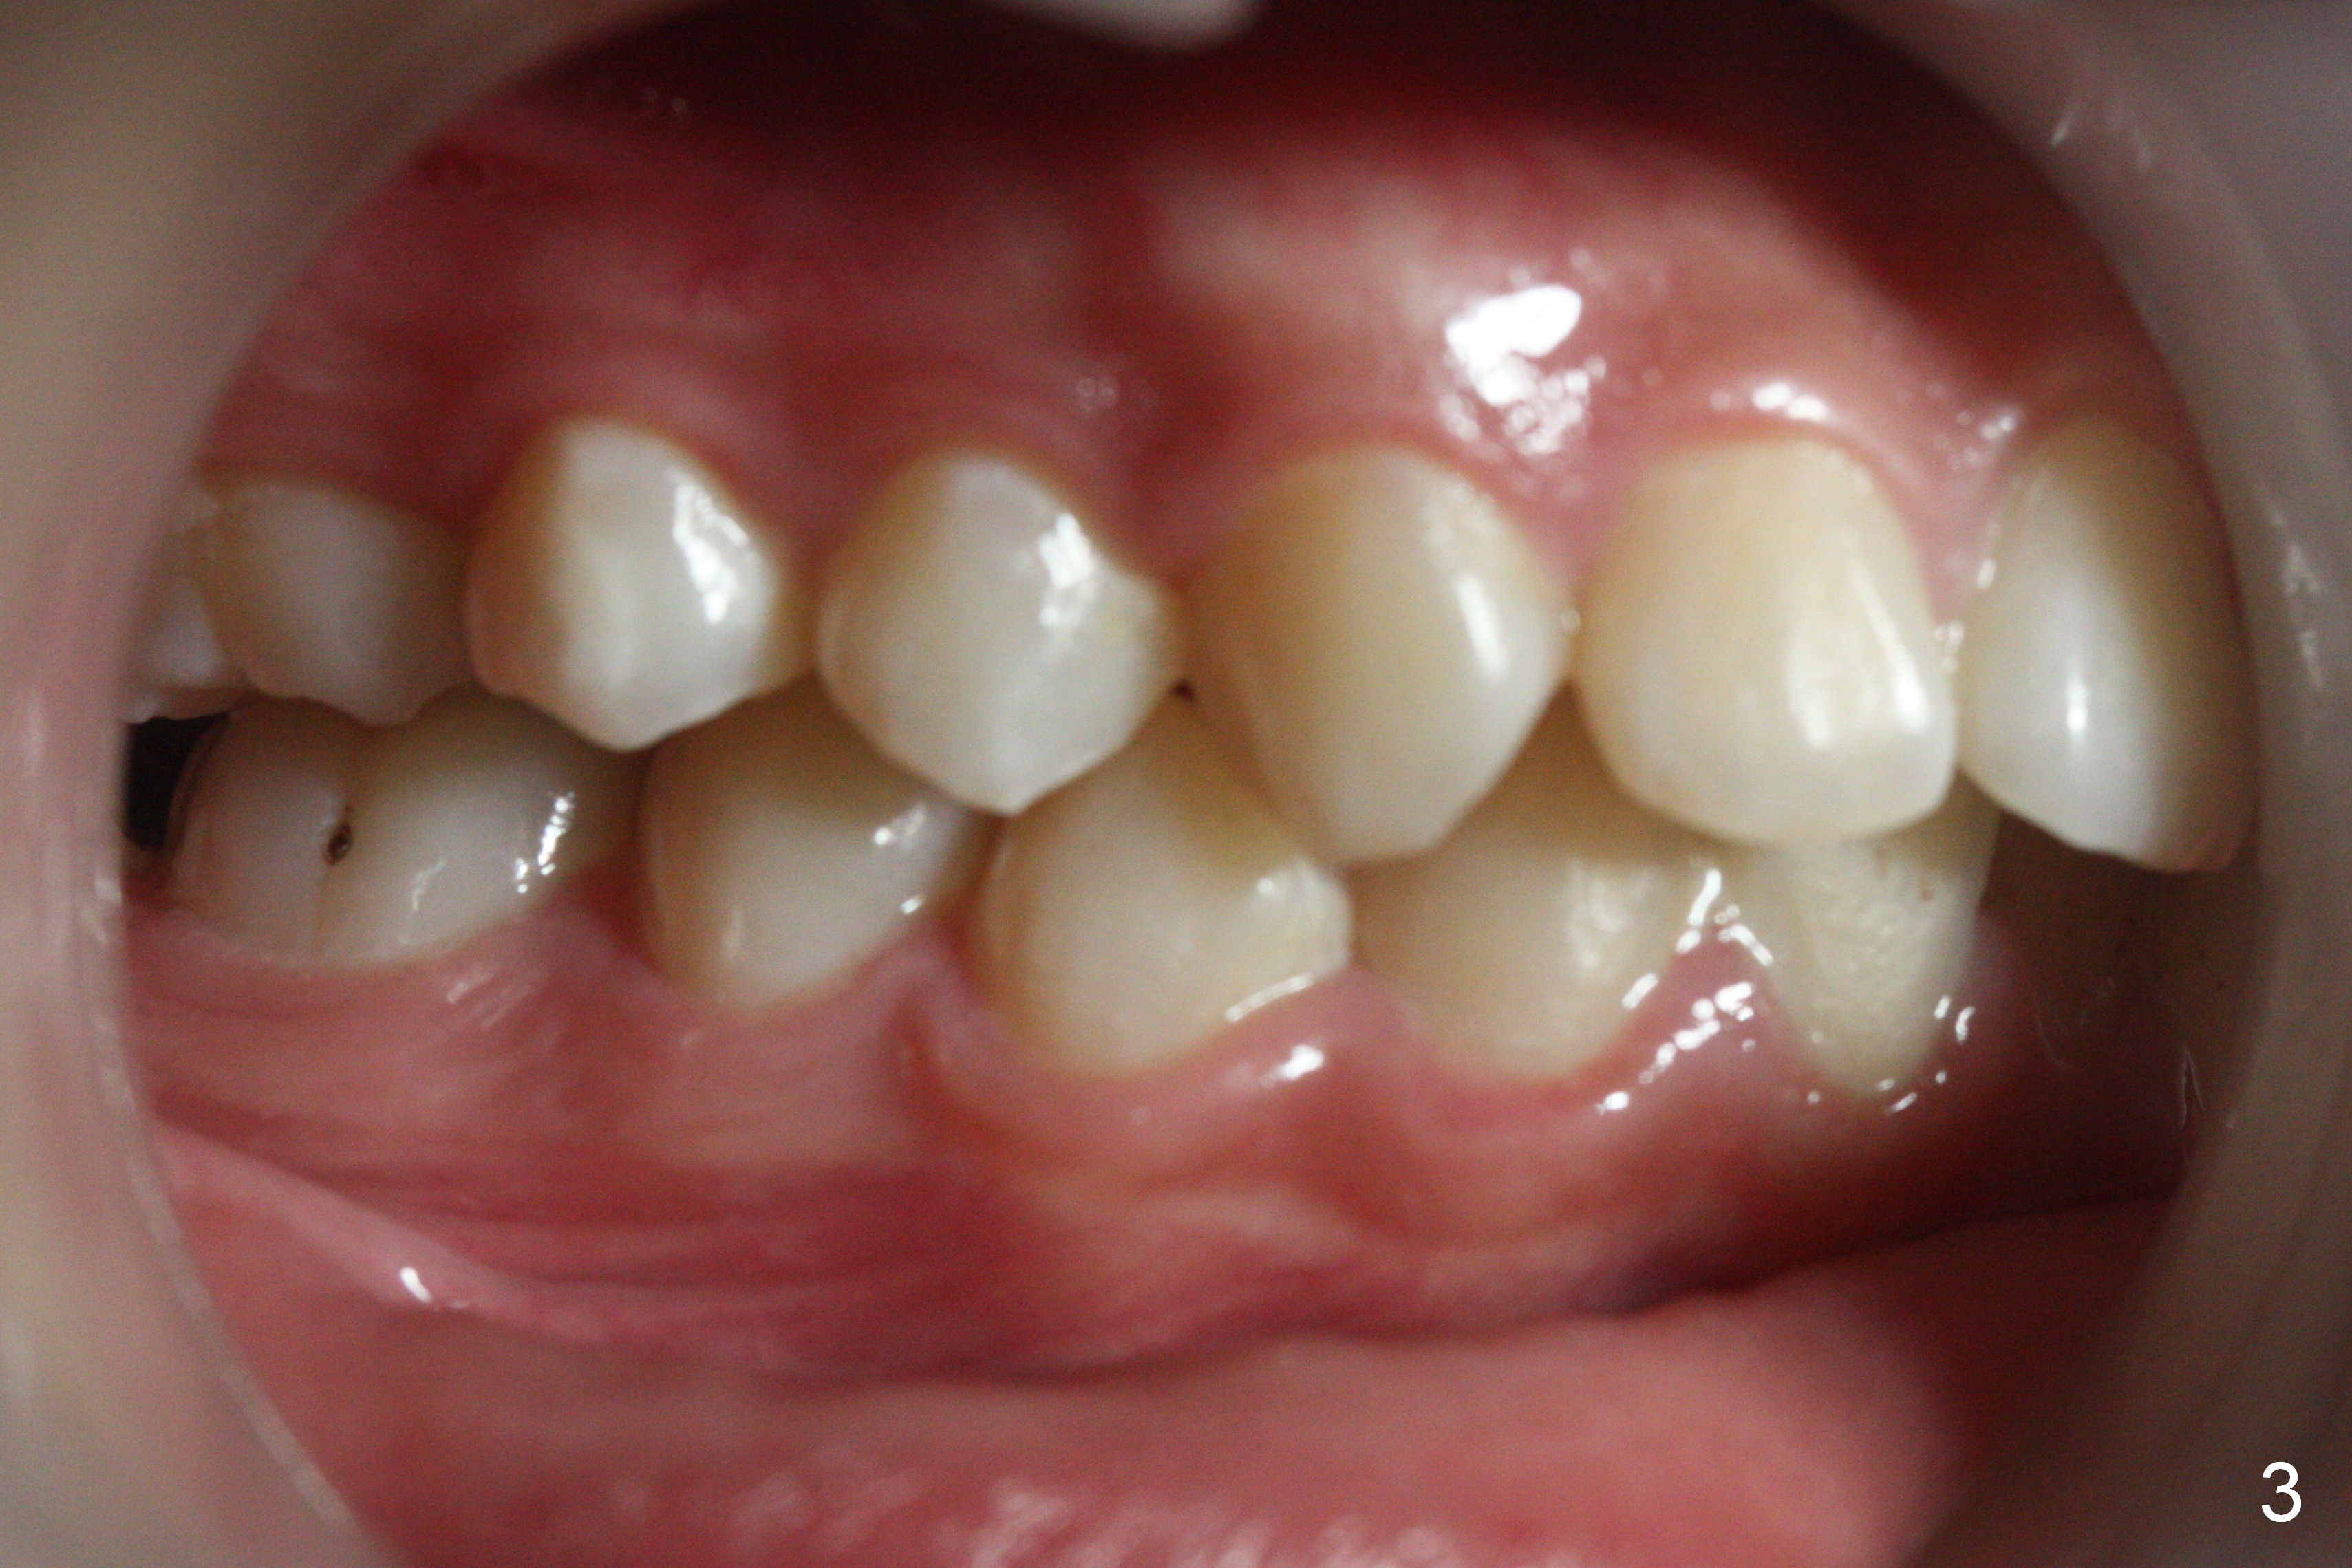

A 17-year-old woman will return for bracketing after caries control and deciduous tooth (Fig.6 arrowheads) extraction. Her profile is slightly protrusive (Fig.1,2). Crowding is more severe in the left posterior region (Fig.4) than the right one (Fig.3). The anterior crowding is also severe (Fig.5). Proximal reduction and use of power chain for constriction will be used instead of extraction of 4 bicuspids. Third molar extraction may have to be done prior to banding, especially for the lower right 2nd molar (Fig.7).

By looking at preop models (Fig.8-13), do you think whether extraction is a better option than non-extraction? Class II occlusion on the right (Fig.8), Class I on the left (Fig.10). With extraction of the 1st bicuspids, the posterior occlusion could be normal with further anterior protrusion (Fig.11). The upper arch is rounded (Fig.12); without extraction, the arch may turn out to be U-shaped. The lower arch is more crowded (Fig.13). Without space, the lower right 2nd molar may not be uprighted (Fig.7).